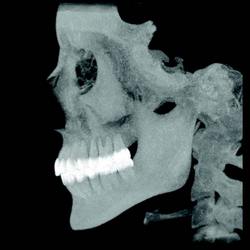

3-D software can shade images to differentiate varying densities of facial structures. Grayscale shading provides the ability to view the relationships of common internal anatomy. Traditional CT imaging renders an 8-bit grayscale (256 shades) or 12-bit grayscale (4,096 shades). Present-day scanners render images in 14-bit grayscale, providing 16,384 shades. Color coding the image by density further distinguishes anatomical structures, enabling the clinician to view pertinent anatomy while planning implant cases, such as nerves and nasal cavities, and mandibular and maxillary dimensions. Segmentation literally cuts the volume rendering, conceding top views, side views, and CT slices that produce unlimited axial, coronal and sagittal views. CBCT slices are as thin as 0.1 mm, compared to 1 mm for a conventional fan CT scan.

CBCT imaging provides comprehensive data and the ability to dynamically manipulate that data, viewing anatomy from multiple perspectives. Diagnosis of TMJ condition and disorder or jaw pathology along with the evaluation of orthodontic cases, airways, impacted teeth and periodontal defects are all facilitated through the use of CBCT imaging.